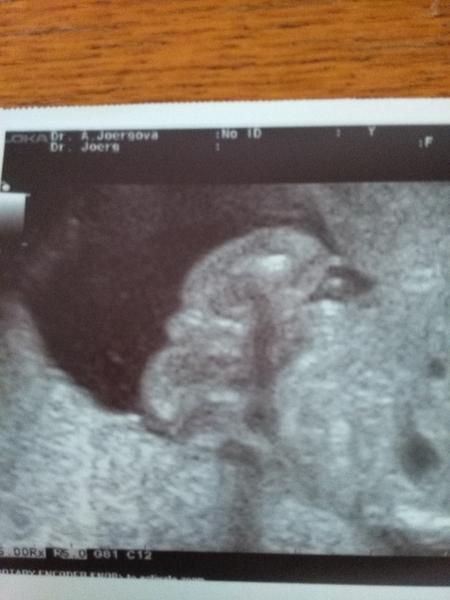

Je to holčička nebo chlapeček? Foto ultrazvuku

Ahoj maminky a budoucí maminky 😉 Prosím, poradila byste mi některá, co vidíte na fotce z ultrazvuku ve 20. týdnu za pohlaví? Určitě jste foteček viděly už mraky, proto vás žádám o radu...Nechci nikoho ovlivnit, proto svůj tip řeknu později 🙂 Děkuju moc!!!

@lucretia7 toť otázka..mě to přijde spíš jako pupeční šňůra..ale může to byt i kluk,ale takhle veliký pytlík snad ještě nemají 😀 co vidíš u mě?foto nad tebou

@gargamelinka Mne to prave taky prijde jako pupecni snoura. Pry je to ale kluk. Ja si nejsem josta, je to moc dlouhe a ma to jiny tvar?

@gargamelinka taky bych se přiklonila ke klukovi, varlata určitě ne, ty takhle malinký mimi ještě dávno nemá v šourku, ale vidím tam jen jednu čárku (ta středová rýha na pinďovi). Holčičky mají čárky tři 🙂 (rýha mezi stydkými pysky a pak po každém boku pysku po jedné).

@elana čárky tam má 3,je to krásné vidět..prý ukázkový kavovy zrno..

Tak co myslite, pindik nebo pupecnik?

@lucretia7 koukni doprostřed zadečku.. Tam je takový malý zrnicko..a za mé u tebe na fotce pupečník takhle velikyho ho nemají..

Ano ano je tam jen pohlaví s nozkama.Nejdriv je světle stehýnko pak pohlaví a tmavší stehýnko